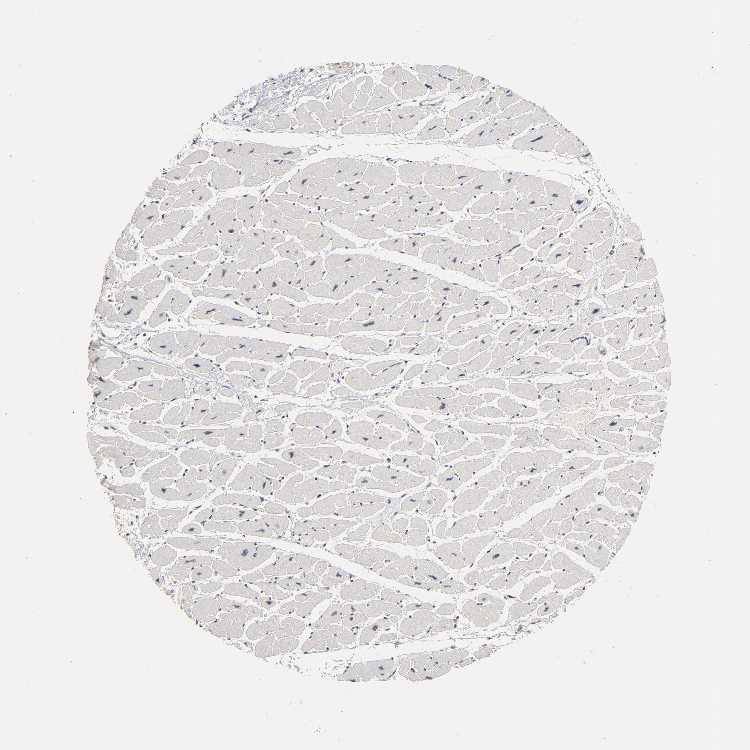

HEART MUSCLE - Antibody stainingi

Antibody staining in the annotated cell types in the current human tissue is reported as not detected, low, medium, or high, based on conventional immunohistochemistry profiling in selected tissues. This score is based on the combination of the staining intensity and fraction of stained cells.

Each image is clickable and will lead to virtual microscopy that enables deeper exploration of all samples and also displays staining intensity scores, fraction scores and subcellular localization as well as patient and tissue information for each sample.

Antibody HPA003128Antibody HPA004112Antibody CAB000146

Cardiomyocytes LowNot detectedLow